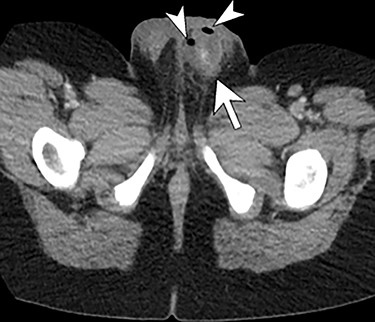

An 11-year-old male presents to the Emergency Department with chief complaints of fever, abdominal pain, nausea and non-bloody vomitus. The patient has no significant past medical history except for a weight that is >95th percentile. The pain started in the periumbilical area and became more generalized. Physical exam showed right lower quadrant (RLQ) pain with guarding with positive obturator sign but no rebound tenderness. An abdominal ultrasound was performed; however, the appendix could not be visualized. The patient then underwent an abdominal computed tomography (CT) that showed a perforated appendicitis. He was immediately taken to the operating room for laparoscopic appendectomy. A perforated appendix with free intraperitoneal pus identified in multiple abdominal quadrants during the operation. The appendix was successfully removed and the patient was transferred to post anesthesia care unit (PACU) in stable condition for recovery. Overnight, the patient developed increasing left scrotal swelling with mild tenderness. Doppler ultrasound showed normal arterial and venous blood flow in both testes, but demonstrated diffuse scrotal wall thickening and inflammation, more pronounced on the left. The patient’s condition failed to improve over the course of next few days and urology was consulted. Repeat ultrasound and a CT scan was obtained, which demonstrated a left intra-scrotal abscess (Figs 1 and 2). Surgical exploration was recommended. At the time of left scrotal exploration, a large intra-scrotal abscess extending into the inguinal canal was identified. Careful examination failed to identify a PPV. The abscess fluid was cultured, drained and the wound irrigated with antibiotic solution. A Penrose drain was placed. The cultures reported rare anaerobic growth of gram-negative rods. He was placed on meropenem and vancomycin at the recommendation of infectious disease. The drain was left in place and he was discharged home with amoxicillin–clavulanate. The drain was later removed on postoperative day five and he recovered fully without sequelae.

Enhanced axial CT scan image through the scrotum re-demonstrates the complex left hemiscrotal collection (arrows) with internal locules of gas (arrowheads).